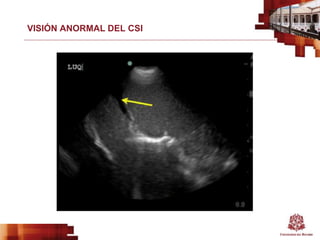

VISIÓN ANORMAL DEL CSI